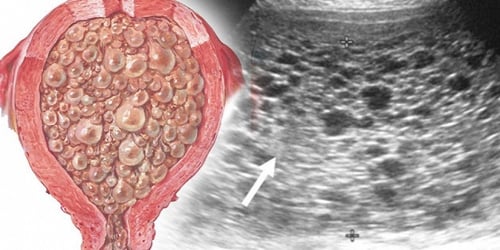

Trường hợp nguyên bào nuôi phát triển quá nhanh khiến tổ chức liên kết trong gai nhau cùng với mạch máu không phát triển theo kịp và bị thoái hóa, phình to và phù nề thành các túi chứa dịch, dính chùm lấy nhau như chùm nho, có đường kích từ 1mm đến vài chục milimet lấn át bào thai và chiếm đầy lòng tử cung. Tình trạng này được gọi là thai trứng (chửa trứng).

Thai trứng xảy ra khi trứng được thụ tinh nhưng thụ tinh bất thường, do tế bào nuôi phát triển quá nhanh, các mô liên kết và mao mạch rốn không phát triển theo kịp, dẫn đến sự phát triển bất thường của gai nhau trong tử cung.